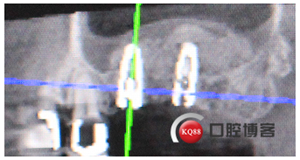

再看看片子。